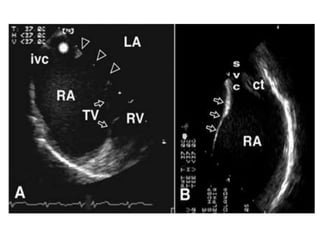

INVESTIGATIONSCBC,RFT-NORMALECHO- SVC Type of ASD                TR Mild                TRPG -45mmHg               PHT-Mod              IVS- Paradoxical Movement              RA/RV Dilated.

ECHOCARDIOGRAPHYEchocardiography reveals atrialseptal defect and most of the pulmonary vein connections in most patients and is the diagnostic modality of choice.Two-dimensional ECHO with color flow Doppler reveals the position and size of the defect and the presence of anomalous pulmonary venous drainage. It also helps identify associated anomalies and reveals the left-to-right (or right-to-left) direction of flow and the degree of right ventricular overload.In children with difficult transthoracic windows, or in older or larger patients, transesophageal echocardiography may be helpful in imaging the defect and pulmonary vein connections.Cardiac magnetic resonance angiography (MRA)/MRI may be alternatively used to complete the diagnostic information needed prior to surgery.

INVESTIGATIONSCBC,RFT-NORMALECHO- SVC Typeof ASD TR Mild TRPG -45mmHg PHT-Mod IVS- Paradoxical Movement RA/RV Dilated.

ECHOCARDIOGRAPHYEchocardiography reveals atrialseptaldefect and most of the pulmonary vein connections in most patients and is the diagnostic modality of choice.Two-dimensional ECHO with color flow Doppler reveals the position and size of the defect and the presence of anomalous pulmonary venous drainage. It also helps identify associated anomalies and reveals the left-to-right (or right-to-left) direction of flow and the degree of right ventricular overload.In children with difficult transthoracic windows, or in older or larger patients, transesophageal echocardiography may be helpful in imaging the defect and pulmonary vein connections.Cardiac magnetic resonance angiography (MRA)/MRI may be alternatively used to complete the diagnostic information needed prior to surgery.